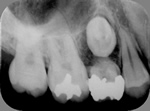

乳歯晩期殊なし

永久歯が前出しない

→

乳歯と永久歯を抜歯し

インプラント埋入